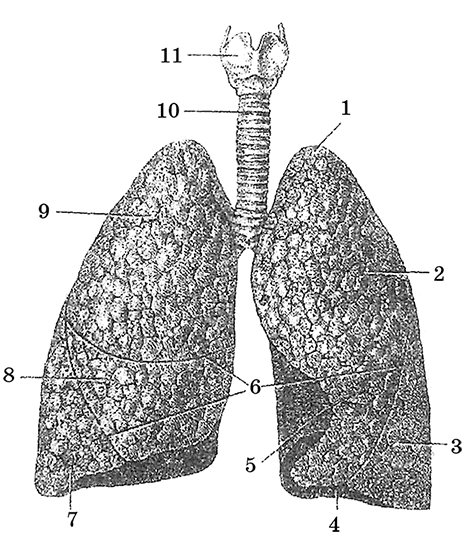

Анатомические изображения сегментов легких различных животных

Раздел: Другие животные